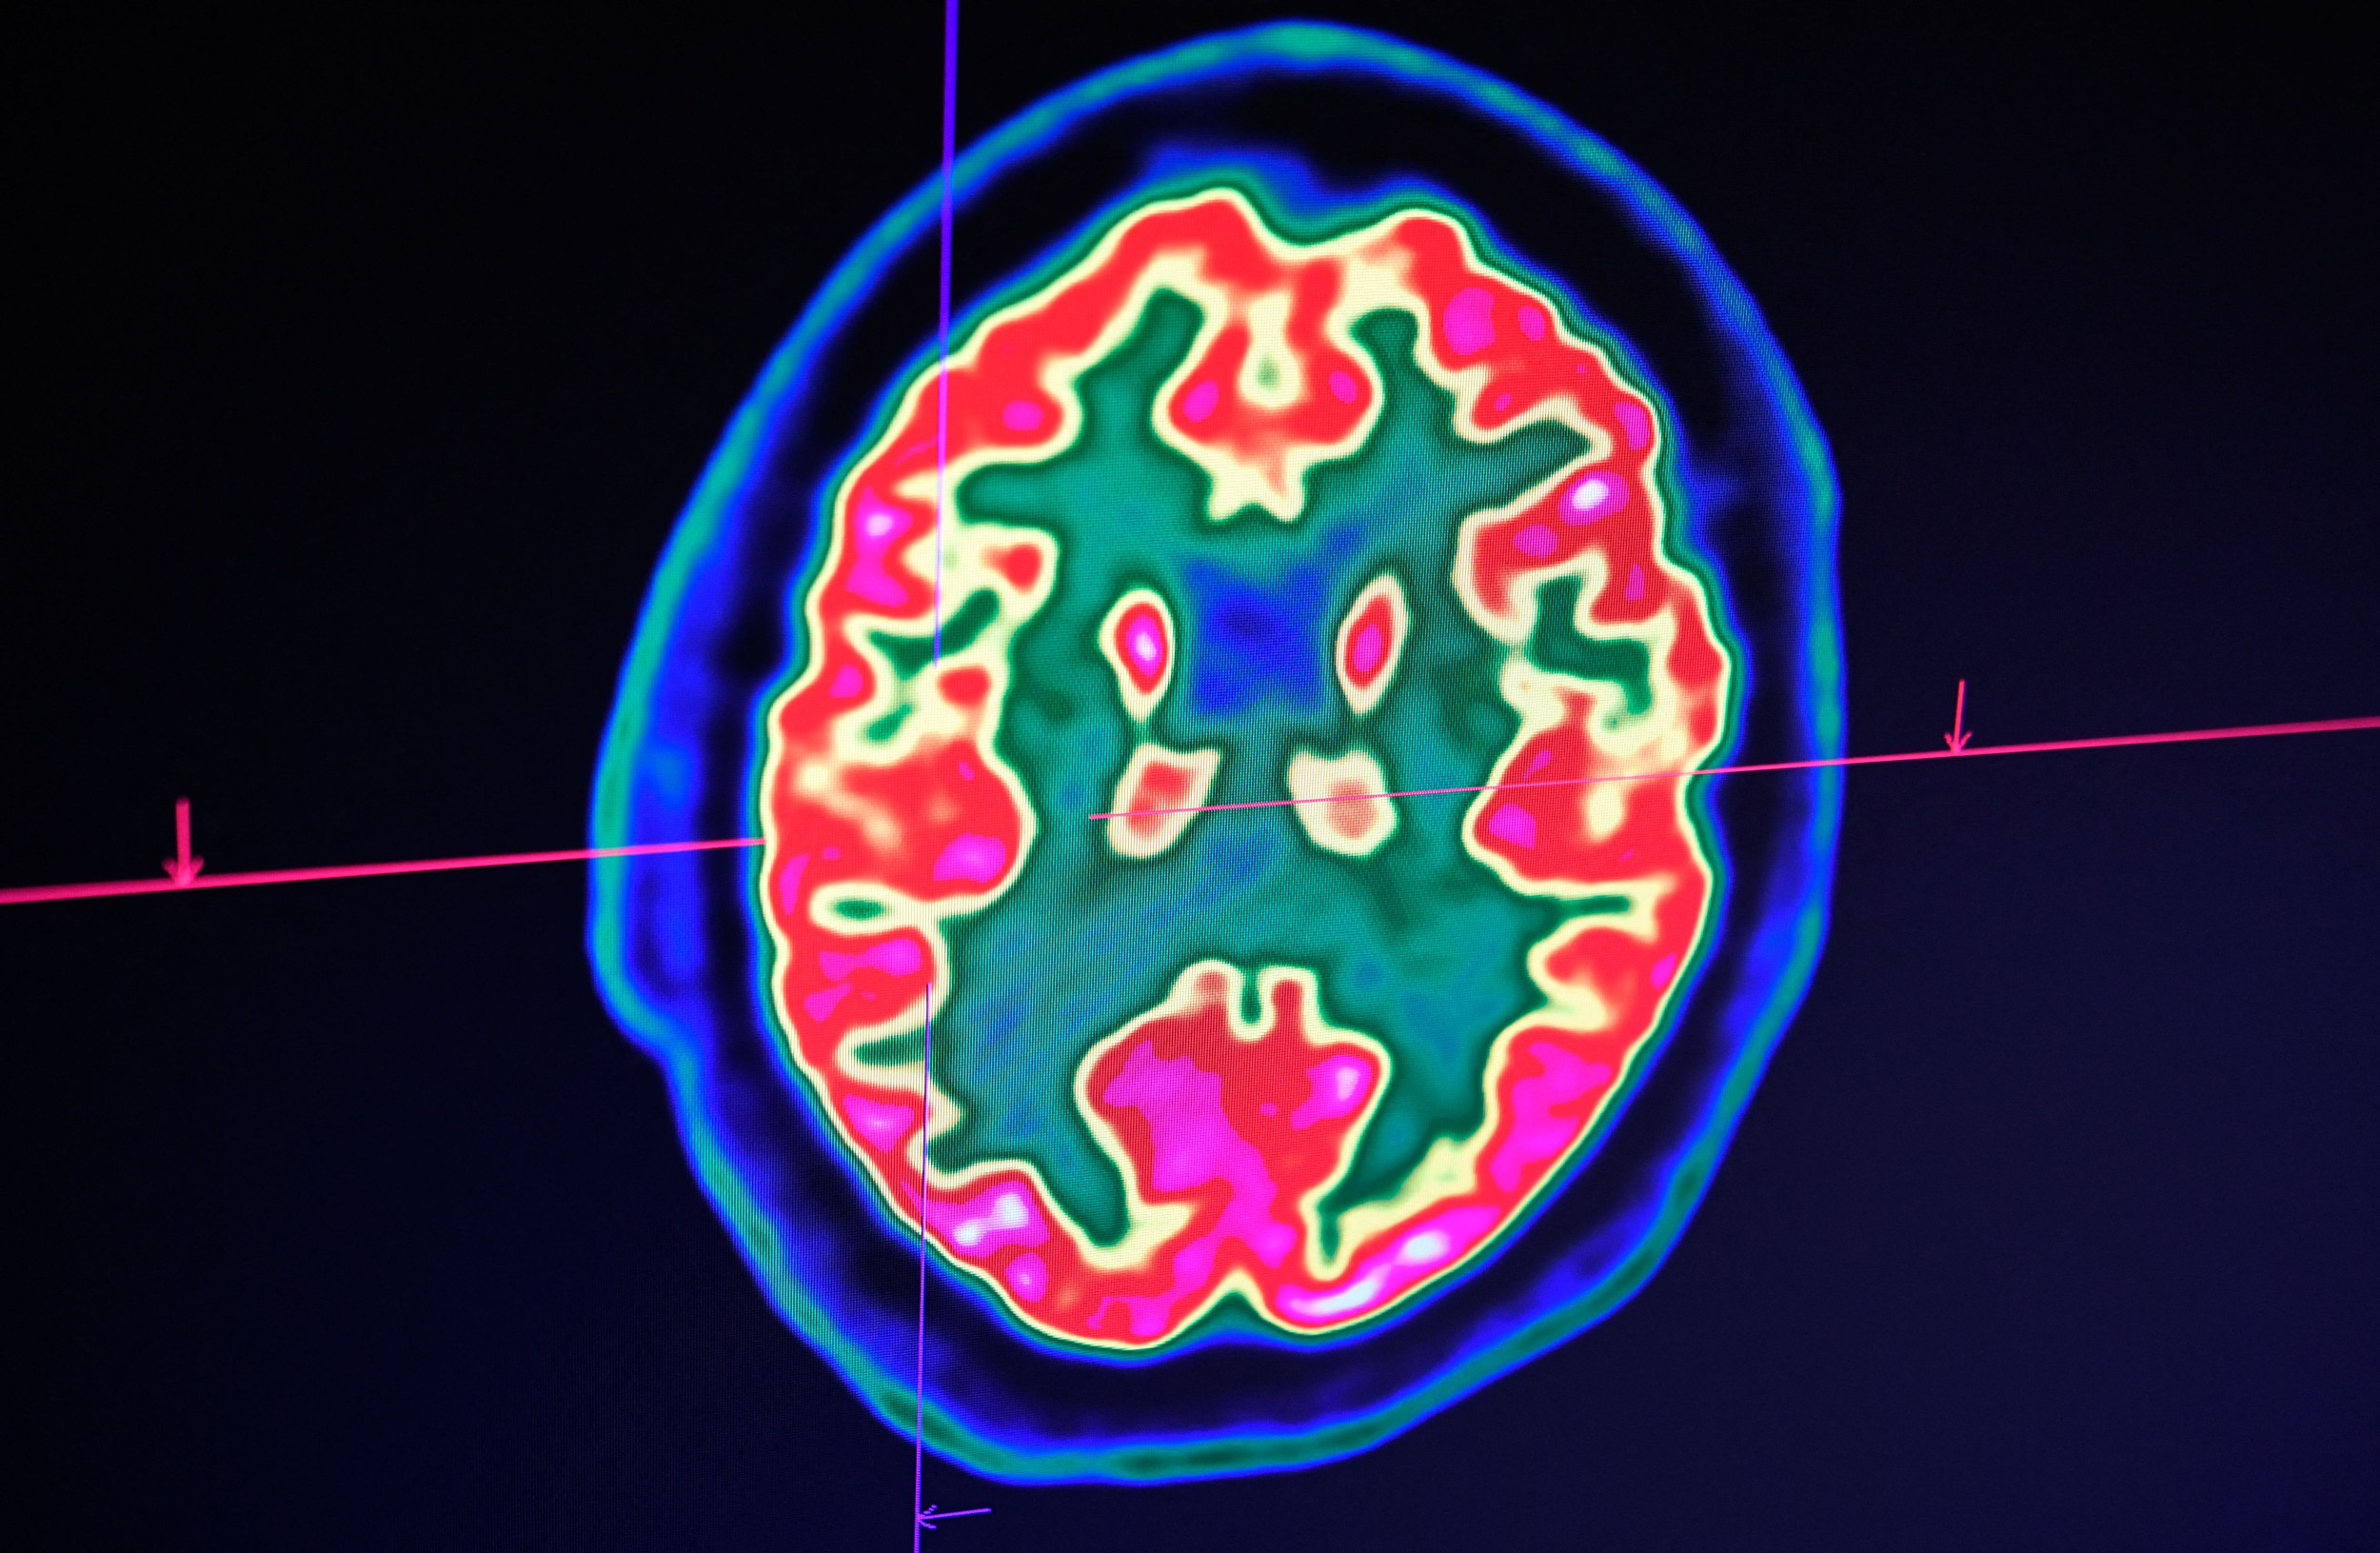

Hence then, the article about promote human flourishing by investing in innovative brain disorder treatments opinion was published today ( ) and is available on Newsweek ( Middle East ) The editorial team at PressBee has edited and verified it, and it may have been modified, fully republished, or quoted. You can read and follow the updates of this news or article from its original source.